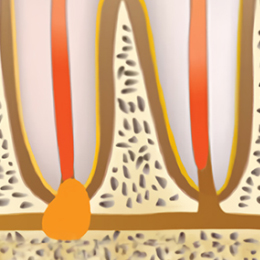

STEP 01

치아의 뿌리 끝 염증 조직을

제거하기 위해 잇몸 쪽으로

치아 뿌리에 접근합니다.

STEP 02

뿌리 끝 부분에

낭종이나 농양 또는

육아종을 확인합니다.